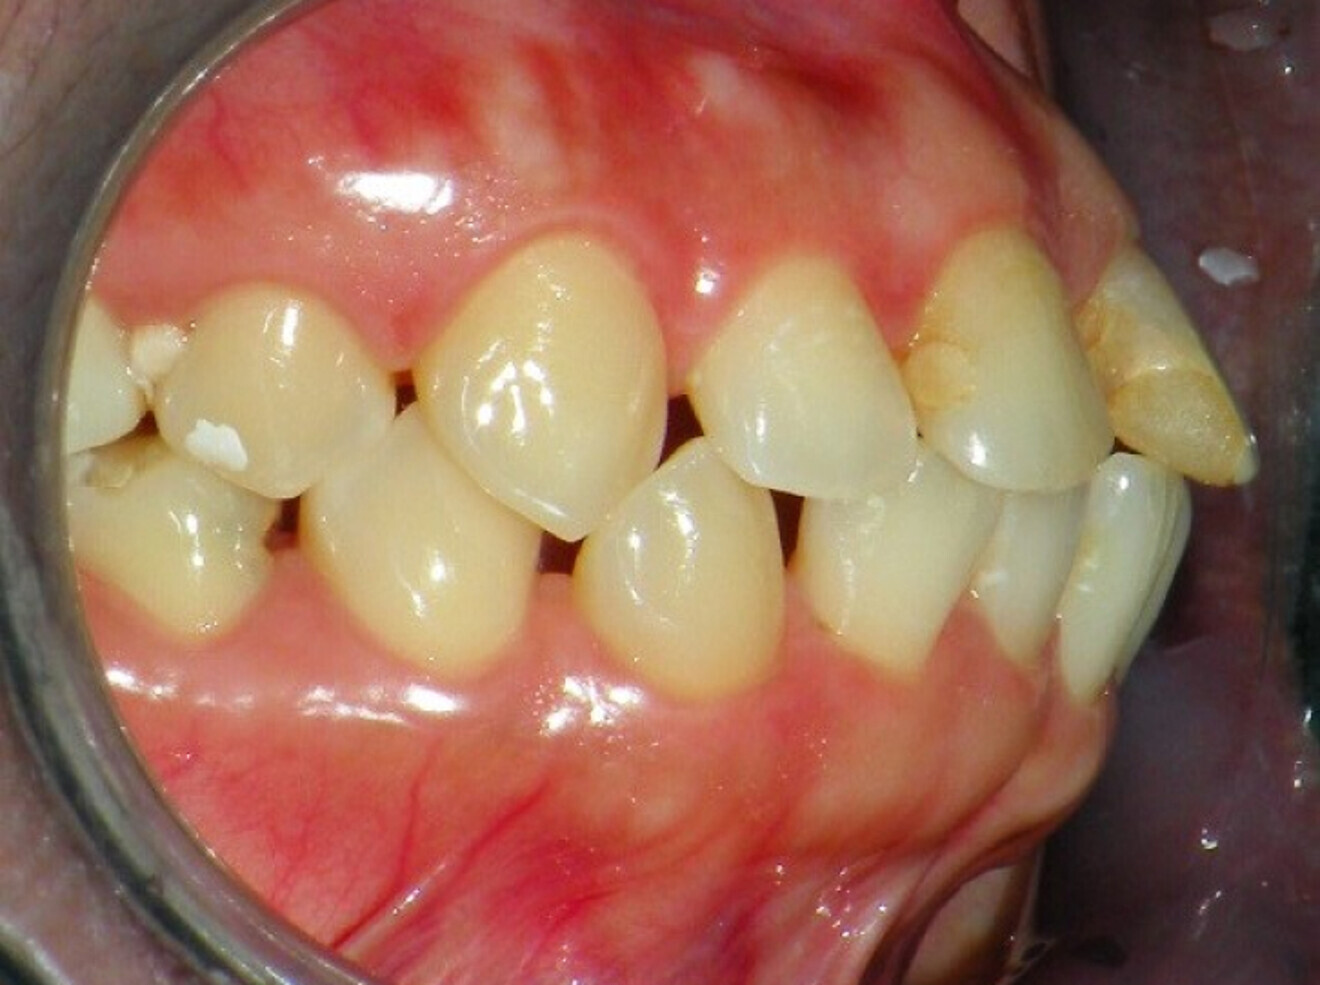

Intra-oral findings:

Class I malocclusion with poli diastemas in both upper and lower arch.

Overbite= 1mm Overjet = 3mm

No molar classification (absence of molars)

Class I canine on right and left side.

Upper midline (mesial to 11) on with face.

Lower midline on with the chin.

Panoramic radiograph analysis:

Missing 18, 16, 25,26, 28, 36, 47 and 48.

20-30% vertical bone loss upper anterior region.